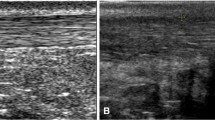

At transversal scans, Hmean, H20, H50, Hsk and Hratio of the distal portions in IT tendons were significantly larger than those in asymptomatic tendons (Table 2), indicating that IT tendons had harder distal portions than asymptomatic controls. The results at longitudinal scans were similar to these found at transversal scans. In Fig. 2, four typical IT tendons were harder than one asymptomatic tendon by visual observation and quantitative comparison.

Distal thirds of Achilles tendons from four subjects with insertional tendinopathy (a–d) and one subject with an asymptomatic tendon (e). The tendinopathic tendons shaded blue and green (a–d) are harder than the asymptomatic tendon which is predominantly green and mixed with small yellow stripes and blue patches (e). Arrows in (a) and (b) indicate calcification. a The quantitative parameters H50 = 0.62, Hratio = 1.30, Hsk = −2.23 and THK = 0.50 cm. b H50 = 0.55, Hratio = 1.14, Hsk = −0.83 and THK = 0.70 cm. c H50 = 0.56, Hratio = 1.42, Hsk = −1.26 and THK = 0.86 cm. d H50 = 0.60, Hratio = 1.27, Hsk = −1.54 and THK = 0.38 cm. e H50 = 0.33, Hratio = 0.67, Hsk = 0.20 and THK = 0.43 cm. H50 and Hsk denote the 50th percentile (median) and skewness of the hardness within tendon, Hratio denotes the mean hardness within tendon to that outside tendon, and THK represents the thickness. The THK in the asymptomatic tendon (e, 0.43 cm) was only a little smaller than that in an IT tendon (a, 0.50 cm) and even larger than that in another IT tendon (d, 0.38 cm); the differences of H50, Hratio and Hsk values between two groups of tendons were much more salient